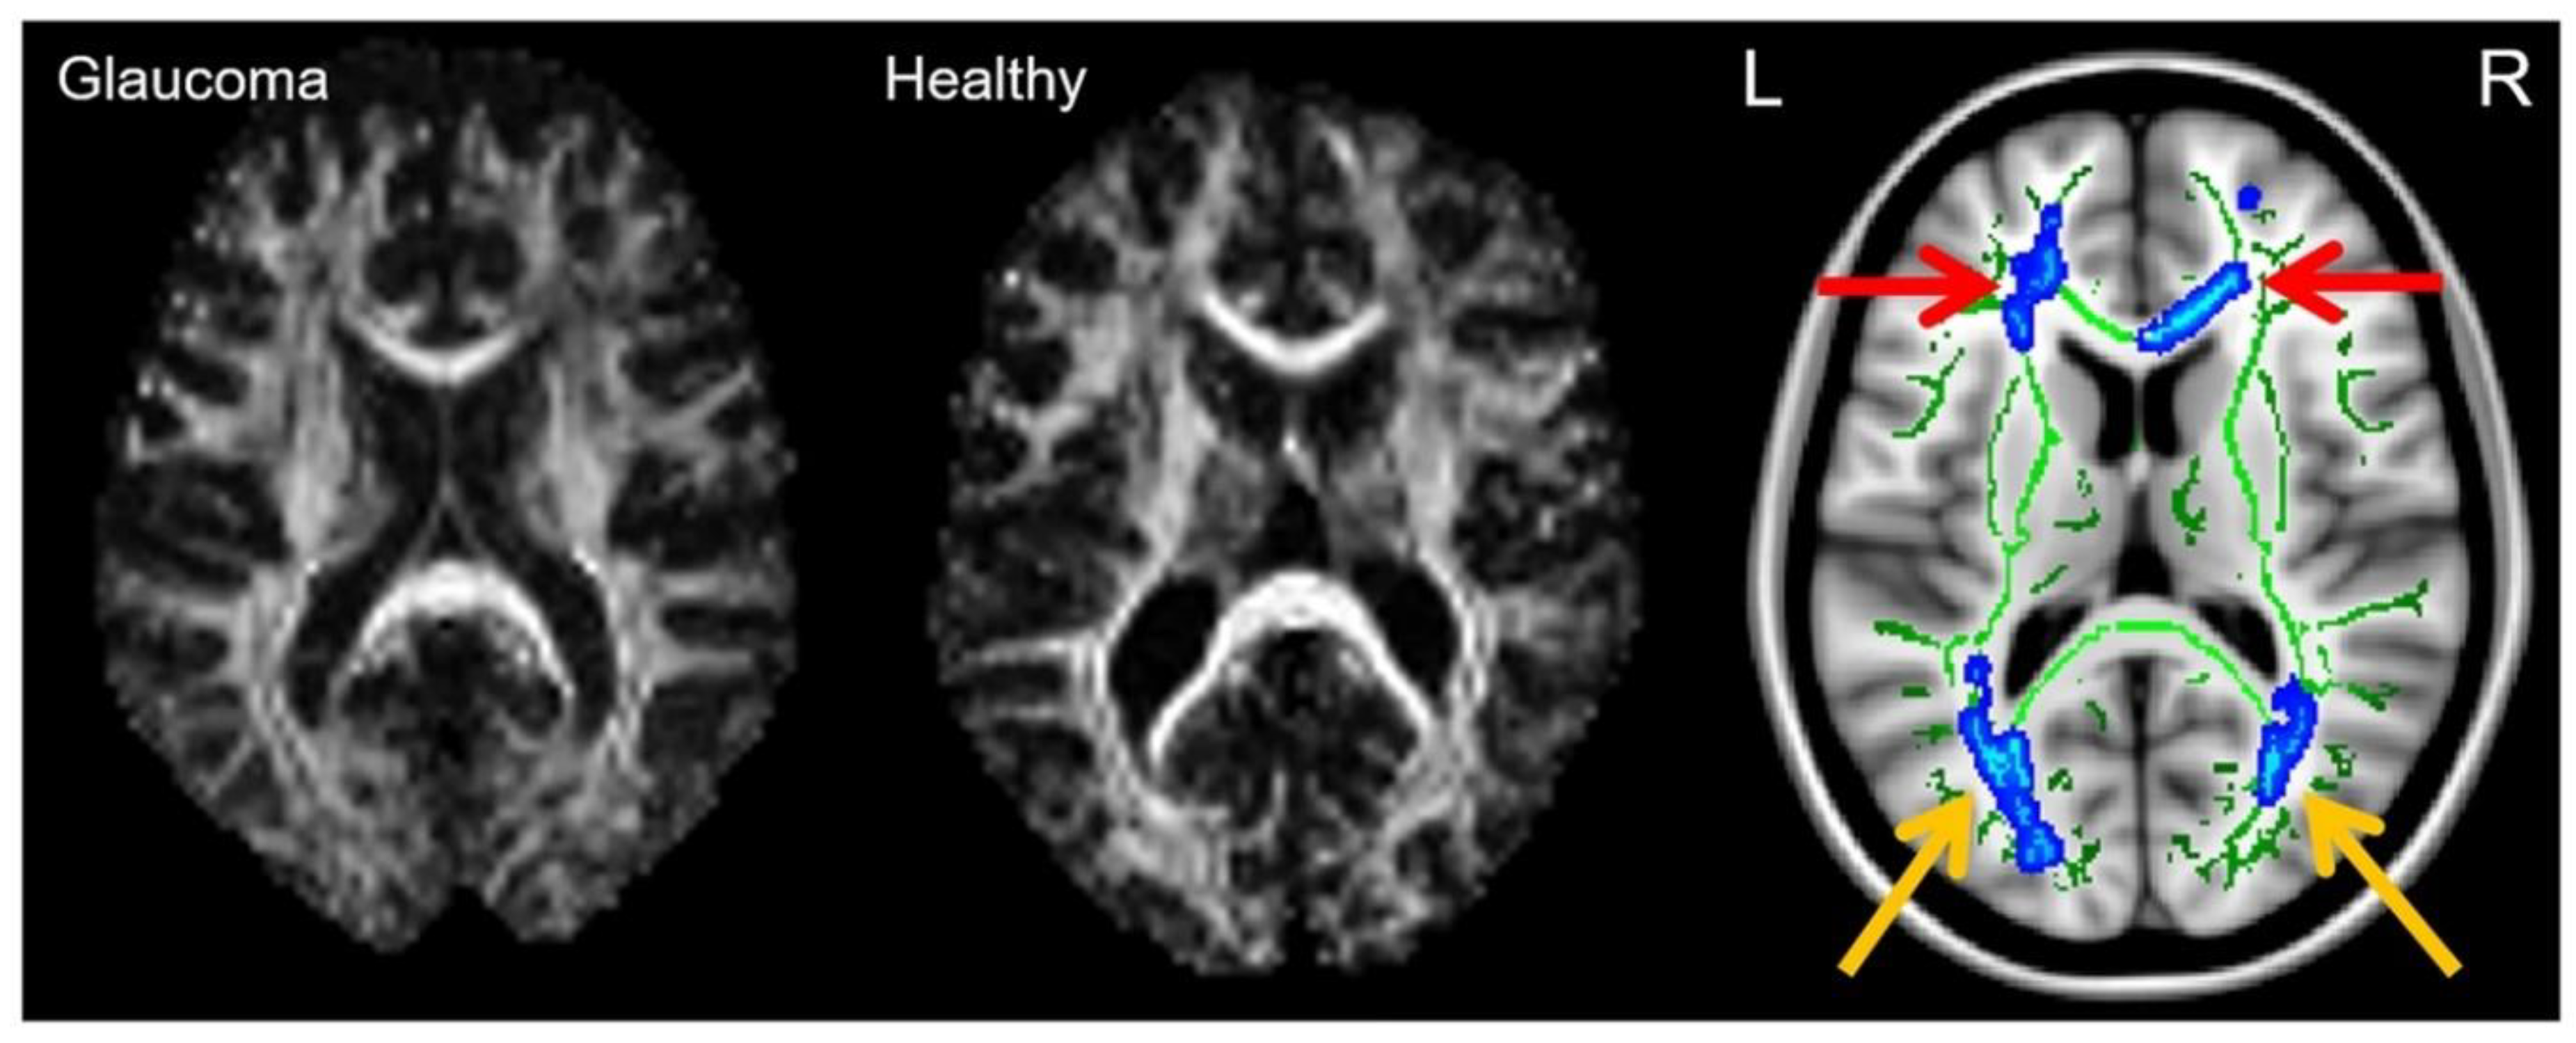

- Lu, P.; Shi, L.; Du, H.; Xie, B.; Li, C.; Li, S.; Liu, T.; Feng, H.; Wang, J. Reduced white matter integrity in primary open-angle glaucoma: A DTI study using tract-based spatial statistics. J. Neuroradiol. 2013, 40, 89–93. [Google Scholar] [CrossRef]

- Dai, H.; Yin, D.; Hu, C.; Morelli, J.N.; Hu, S.; Yan, X.; Xu, D. Whole-brain voxel-based analysis of diffusion tensor MRI parameters in patients with primary open angle glaucoma and correlation with clinical glaucoma stage. Neuroradiology 2012, 55, 233–243. [Google Scholar] [CrossRef]

- Hanekamp, S.; Ćurčić-Blake, B.; Caron, B.; McPherson, B.; Timmer, A.; Prins, D.; Boucard, C.C.; Yoshida, M.; Ida, M.; Hunt, D.; et al. White matter alterations in glaucoma and monocular blindness differ outside the visual system. Sci. Rep. 2021, 11, 6866. [Google Scholar] [CrossRef] [PubMed]